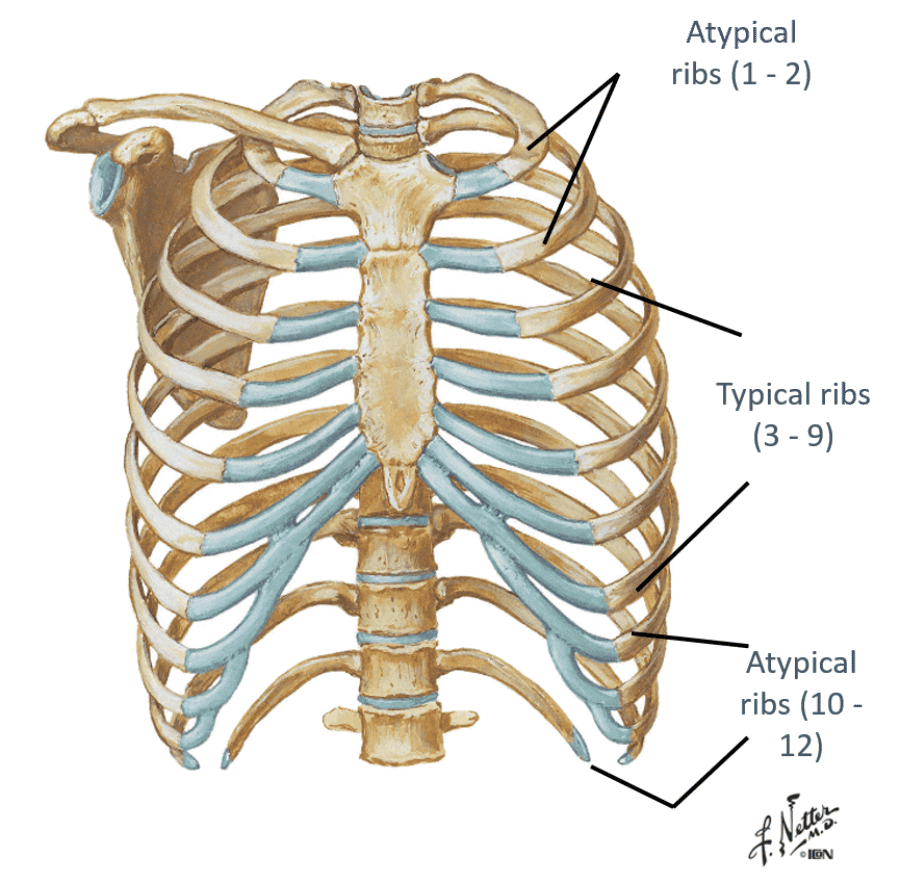

describe typical vs. atypical ribs?

- Typical ribs = 3-9...have all the "usual" landmarks of the rib

- Atypical ribs = 1,2 10-12...dont have the typical landmarks that a rib would have

Identify the landmarks of a typical rib?

Head (H)

Neck

(N)

Tubercle (T)

Shaft/body (S/B)

Costal angle (CA)

look at picture

the head of a typical rib has what that do what?

what does the tubercle articulate with?

how would you describe the shaft/body region?

what is the costal angle a common site for?why is that?

Have facets (F) that articulate with two different vertebrae

Tubercle (T)...articulates with transverse process

Shaft/body (S/B)...thin, flat portion

Costal angle (CA)...common site of rib fracture, weakest point of the rib